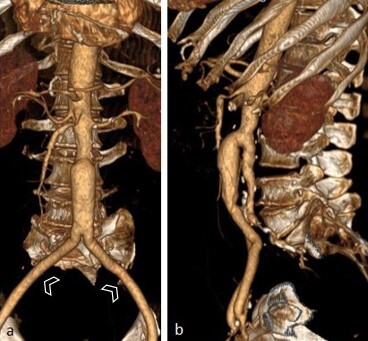

Persistent double dorsal aorta is an extremely rare congenital anomaly, with only 13 cases published to date. The objective of this study is to present this embryological variant as observed in the abdominal aorta of a patient. The anatomical description was written up on the basis of a review of electronic medical records and imaging exams. The patient in this case was an elderly 79-year-old man who presented at emergency with pain at rest in the left lower limb. He was admitted and laboratory tests and imaging exams were ordered. The variation was an imaging finding observed on angiotomography, consisting of complete separation of the abdominal aorta into two portions - a ventral and a dorsal, with different calibers - at the level of the third lumbar vertebra. There was also an anomalous origin of the inferior mesenteric artery.